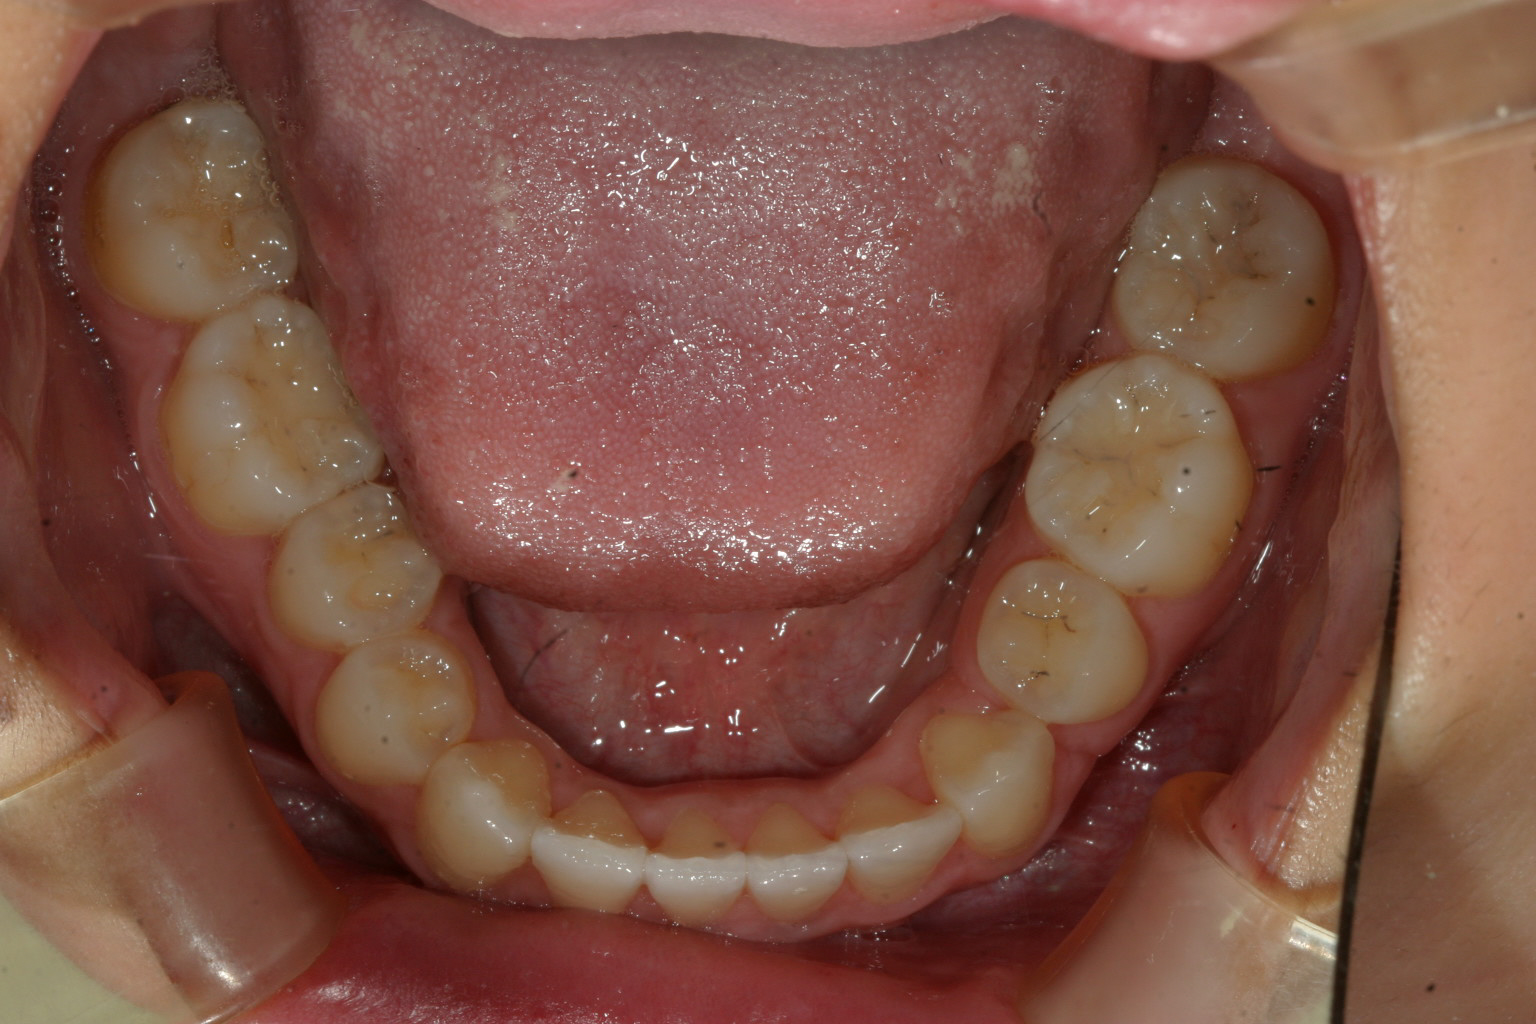

下顎は左側小臼歯1本抜歯する事で改善しました。

綺麗に被蓋関係も出来受け口改善しました。

今回のインビザラインケースは小臼歯1歯抜歯する事で受け口の改善を試みました。

私としましては出来るだけ抜歯せずに治療したい派なんですが必要最小限の1歯で何とか

治療出来て良かったと思っています。